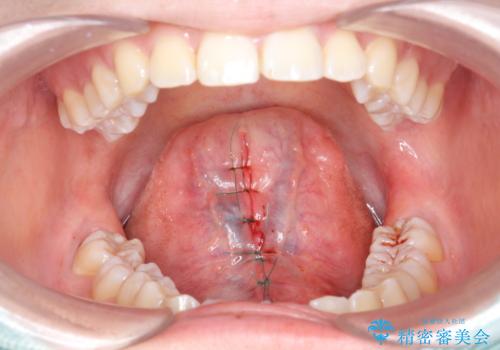

- 舌が動かしにくいとの事で来院。

局所麻酔を行い、舌小帯切除術を行いました。

舌の可動範囲が広がり満足していただけました。